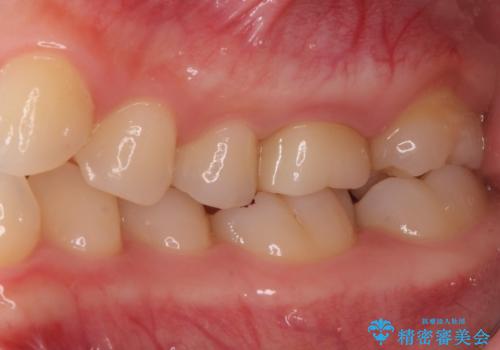

金属の奥歯 → 白い奥歯 根管治療からのやり直し

- 再根管治療→土台の築造 を行った上でのかぶせ物のやり替えをおこないました。

神経の無い歯のかぶせ物をやり替える際は、是非根管治療からしっかりやり直すことをおすすめします。

かぶせ物の種類:Bellezza